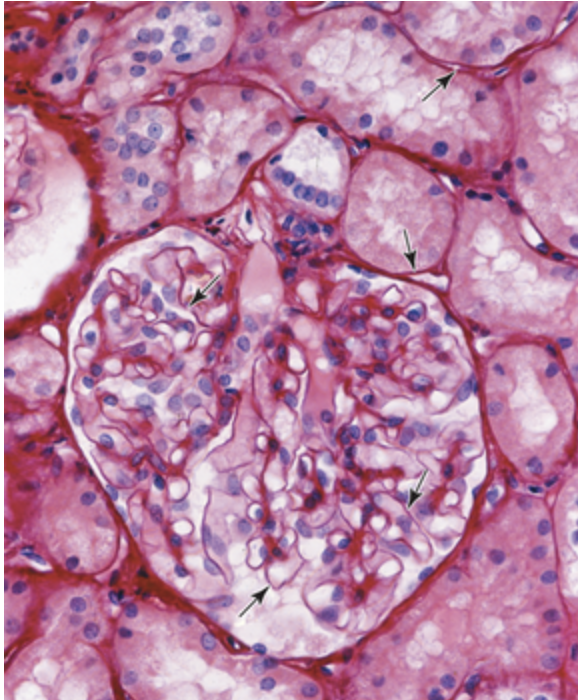

In this picture, a section of kidney is shown. The main roles of the structures highlighted by the arrow include…

SUPPORT AND FILTERING

The basal surface of all epithelia rests on a thin extracellular, felt-like sheet of macromolecules referred to as the basement membrane, a semipermeable filter for substances reaching epithelial cells from below. Nearest the epithelial yaer is an electron dense layer, 20-100 nm thick, consisting of a network of fine fibrils that comprise the basal lamina and beneath this layer is a more diffuse and fibrous reticular lamina. The terms “basement membrane” and “basal lamina” are sometimes used interchangeably, but “basal lamina” usually denotes the fine extracellular layer seen ultrastructurally and “basement membrane” the entire structure beneath the epithelial cells visible with the light microscope.